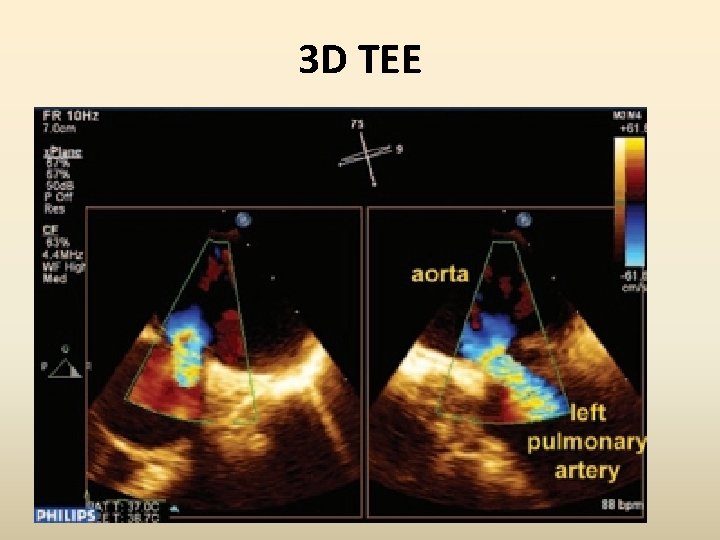

3 D TEE